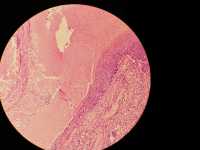

女

年龄

54

眼睑1㎝大小包块

眼睑肿块

1㎝大小

增生性毛母质瘤?

考虑符合:

毛母质瘤

钙化上皮瘤(或毛母质瘤)。